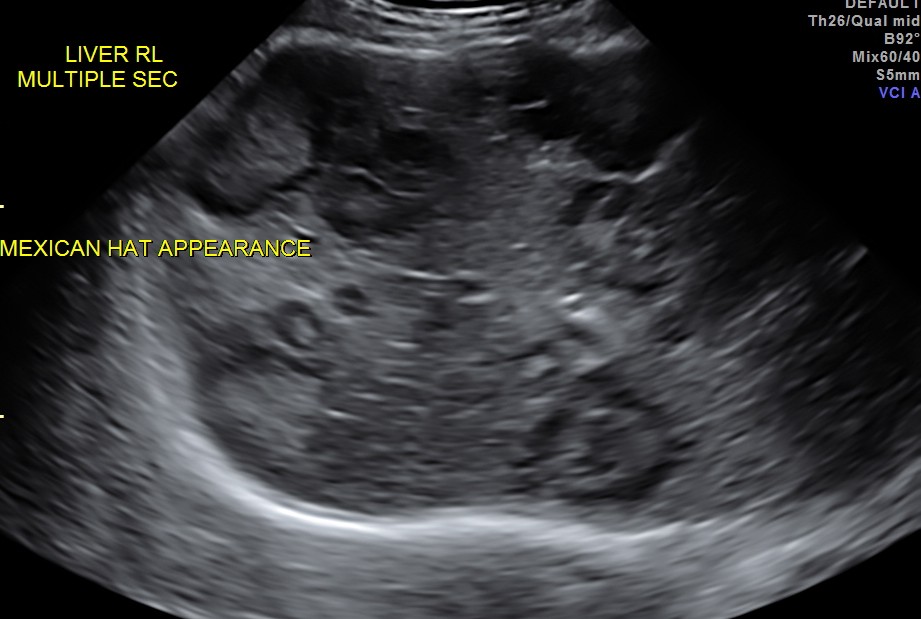

His liver showed multiple secondaries .

secondaries show target appearance or bird’s eye view of mexican hat appearance

DISCUSSION : Generally the target sign or the bird’s eye view of the Mexican hat sign could signify colo-rectal carcinoma.